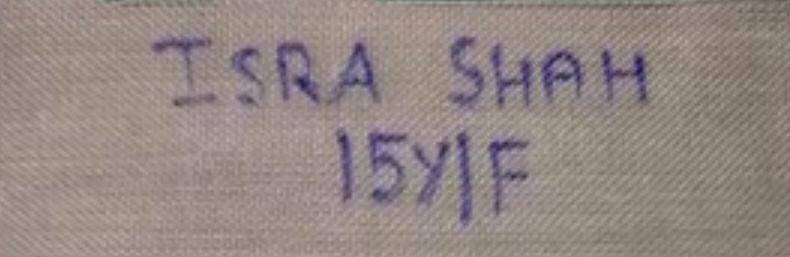

વડોદરાની સયાજી હોસ્પિટલમાંથી આજે એક અજીબો-ગરીબ પરંતુ ચેતવણીરૂપ કિસ્સો પ્રકાશમાં આવ્યો છે. મુંબઈથી સગા સંબંધીઓને મળવા વડોદરા આવેલી 15 વર્ષીય ઇશરા શાહ નામની કિશોરી અચાનક હિજાબમાં લગાવવામાં આવતી 4mmની તીક્ષ્ણ પિન ગળી ગઈ, જેના કારણે તેનો જીવ જોખમમાં મુકાઈ ગયો હતો.

ઘટના બન્યાના માત્ર બે-ત્રણ કલાકમાં જ કિશોરીને સયાજી હોસ્પિટલમાં લાવવામાં આવી હતી. તપાસ દરમિયાન કરાયેલા એક્સ-રેમાં ખુલ્યું કે પિન શ્વાસનળીના વિભાજન ભાગ પાસે ડાબી બાજુના નીચેના ફેફસાંમાં અટવાઈ ગઈ હતી. પરિસ્થિતિની ગંભીરતા જોતા તાત્કાલિક એનેસ્થેશિયા નિષ્ણાતની મદદથી કિશોરીને ઓપરેશન થિયેટરમાં લઈ જવામાં આવી.